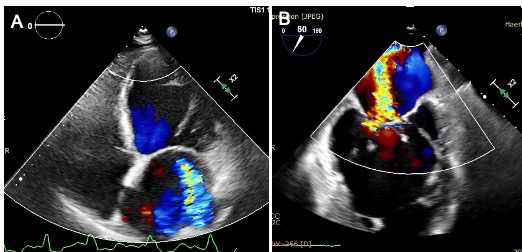

术前经胸和食道超声结果。左图:经胸超声提示心房心室扩大,二尖瓣重度反流;右图:食道超声提示二尖瓣重度反流(彩色血流)。

家住黑龙江省黑河市,今年71岁的王大爷(化姓)两年前出现了活动后呼吸困难的症状,休息后有所缓解,在此其间反复就诊于当地医院,但内科保守治疗均无效,症状没有缓解。一个月前王大爷呼吸困难加重,心悸、乏力,无法平卧,情况危急,家人立即将其送至beat365在线唯一官网二院。经检查确诊为心功能不全,二尖瓣重度反流,左心室舒张末内径显着扩大至68 mm,LVEF(心脏射血分数)降低为38%,心衰标志物NT-proBNP高达23072 pg/ml。经过规范的一个月的抗心衰药物治疗后,患者的症状仍未缓解,而且本次入院后超声提示LVEF为32%,二尖瓣仍为重度反流。但该患者已年逾七旬、体质弱、心功能差,属传统外科开胸手术高危人群。